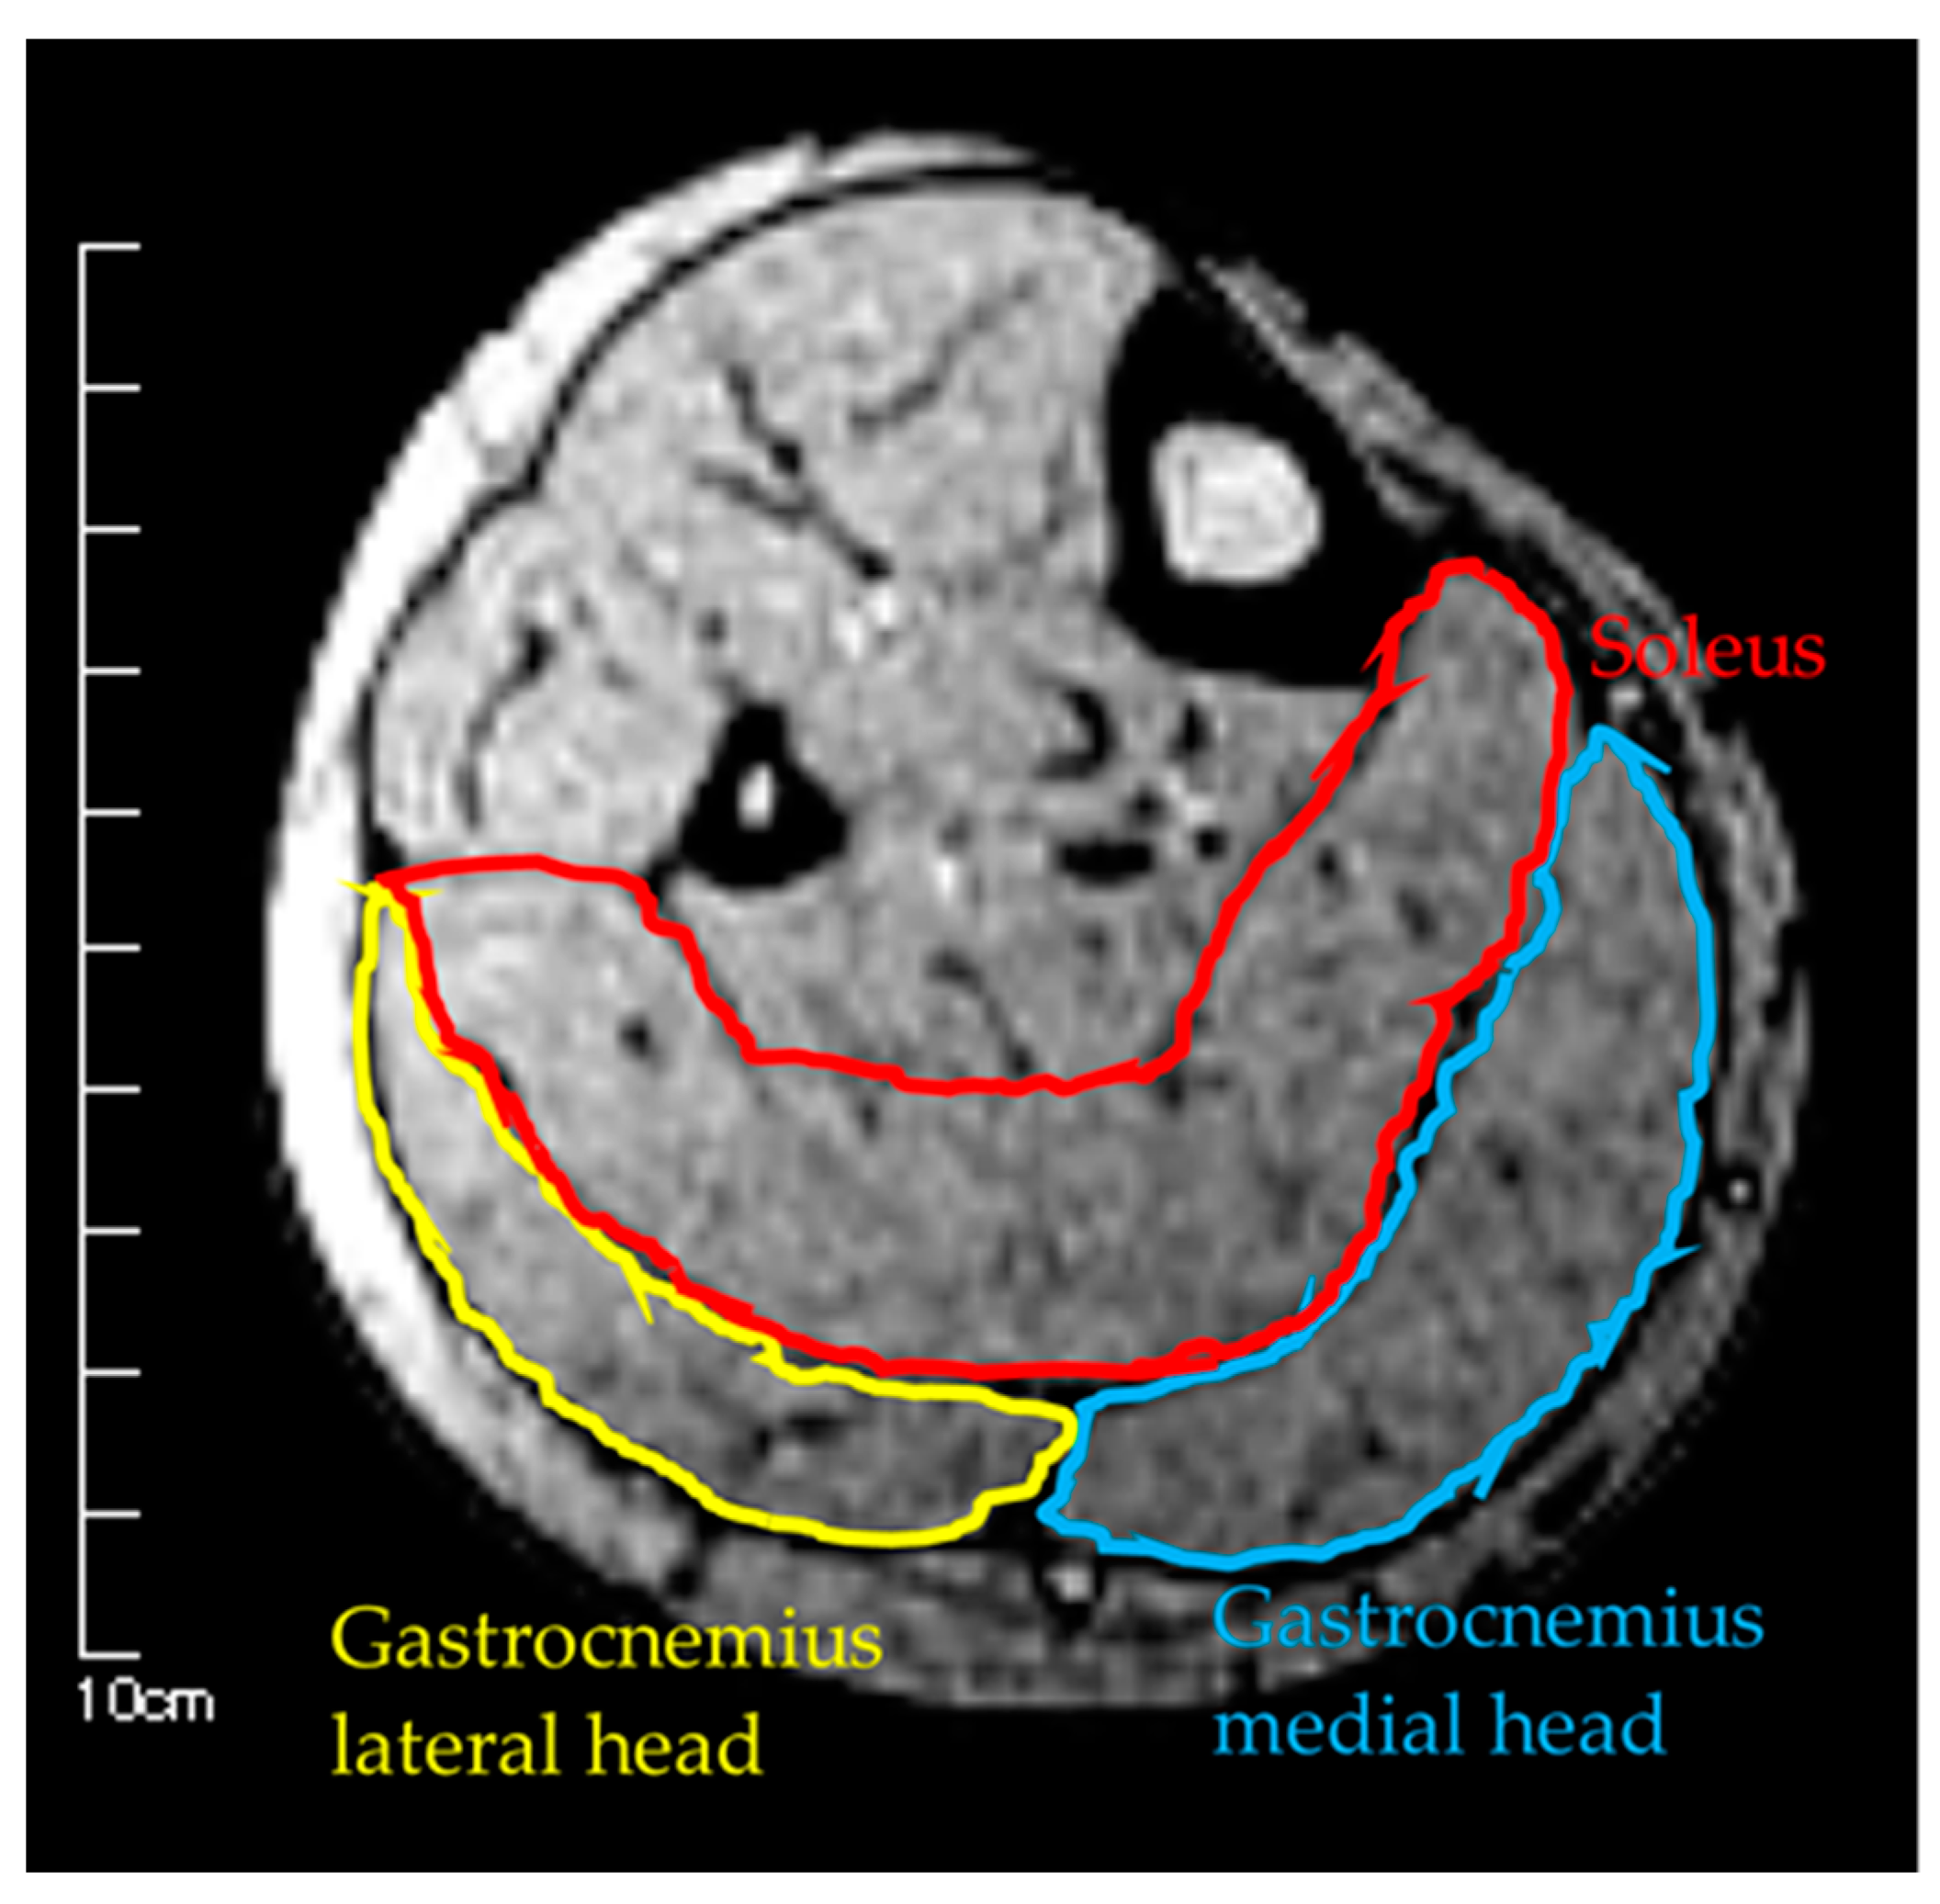

Figure 2.

Measurement of muscle cross-sectional area by MRI.

Measurements were taken in three conditions: (1) MRI in the supine position, (2) MRI in the sitting position, and (3) US imaging in the sitting position. The sitting position was chosen for the measurement of the antigravity position because it is easy to hold the limb position with little motion in the antigravity position. In the supine position for MRI, the foot was placed on a pedestal in a supine position in which the hip and knee joints were flexed at 90°, and the foot was supported only by the heel to prevent the triceps surae from changing its shape due to contact with the pedestal. In addition, a plate was placed perpendicular to the floor at the plantar part of the foot to maintain dorsiflexion at 0°. MRI and US imaging in the sitting position were performed in a chair (with a backrest) with the knee joint flexion at 90°, the lower leg perpendicular to the floor, and the ankle joint dorsiflexion at 0° as in the supine position. In all measurements, the thigh was fixed with cushions and bands to prevent the lower leg from moving during the imaging, and the participants were instructed to hold it as much as possible. Using vertical MRI with a 0.4 T permanent magnet, (Hitachi Healthcare, Ltd., Tokyo, Japan), horizontal T1-weighted images were obtained from the fibular head to the 290 mm distal end at 10 mm intervals (Figure 1). The imaging parameters were as follows: slice plane axial; pulse sequence RF-spoiled steady-state gradient echo; field of view, 280 mm; repetition time, 110.0 ms; echo time, 8.6 ms; flip angle, 35°; slice thickness, 10.0 mm; slice interval, 10.0 mm; matrix size, 256 × 256; number of signals, average of 2; receiver bandwidth, 20.6 kHz; and scan time, 4 min and 32 s. Using the image analysis program ZedView (LEXI Co., Ltd., Tokyo, Japan), the muscles were identified based on the boundary of the fascia of the soleus (SOL), gastrocnemius medial head (GM), and gastrocnemius lateral head (GL) using the acquired images, and the areas marked on the images were measured as the MCSA of each muscle (Figure 2). The 10 mm slice areas of MRI were summed, and the volume of each muscle was calculated using a ZedView. The images of the SOL, GM, and GL were taken by US using a linear probe (7.5 MHz) in B-mode MyLab25 (Esaote, Florence, Italy). Short-axis images were taken at 20.0 mm intervals from the peroneal head in each muscle by applying a probe to the center of the ventral region of the muscle on the horizontal plane. We used a hard-type gel (LOGIQLEAN, GE Healthcare Japan, Tokyo, Japan), which is flexible and easy to keep in shape, to avoid direct contact between the probe and the lower leg. Indirect contact through the gel avoids the effects of pressure exerted by the probe on the lower leg. In addition, to maintain the position of the probe at the time of measurement, we marked the lower leg prior to the measurement, following which assessments were made based on the marking. For the measurement of MT, the maximum length of each muscle was measured with respect to the boundary of the fascia using the image analysis program Image J (Figure 3). The average value of the two measurements was calculated and used as the MT value. MRI, US imaging, and MCSA and MT measurements were performed by the same examiner.